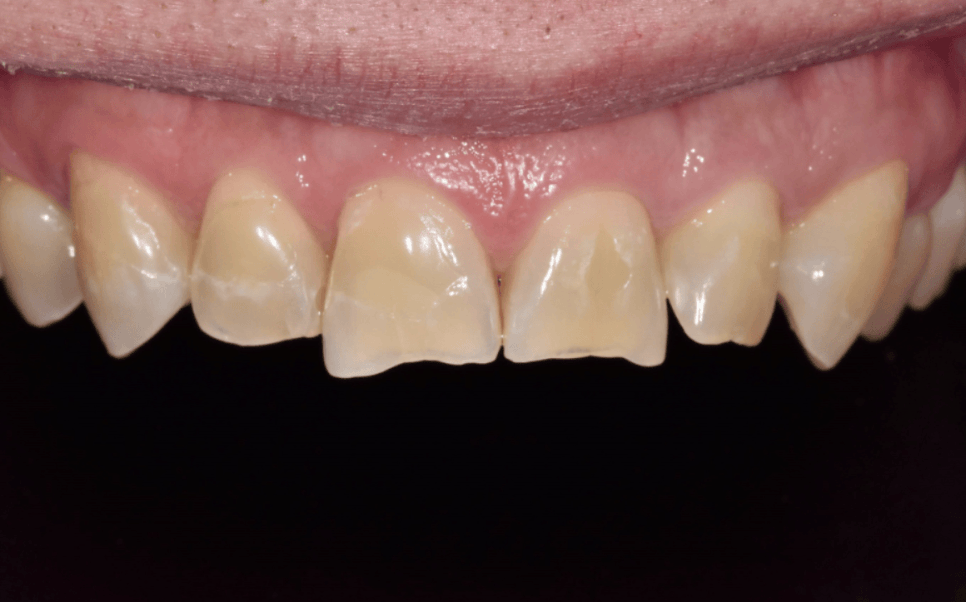

이 환자분은 앞니로 꽃게를 드시다가

앞니 끝(절단은)이 깨져 내원하셨습니다.

사진과 검사상 다행히도

신경이나 뿌리까지 금이 이어진 흔적은

보이지 않았습니다.

교합을 확인했을 때도

위 앞니가 아래 앞니를 살짝 덮는

정상 범주의 교합이어서,

레진으로 수복하더라도

쉽게 다시 깨질 가능성은 높지 않은 상태였습니다.

그래서 내원한 당일에 레진으로

자연스럽게 앞니 형태를 회복해 드렸습니다.

환자분도 깨지기 전 모습 그대로 돌아온

앞니를 보시며 안도하시는 표정이셨습니다.